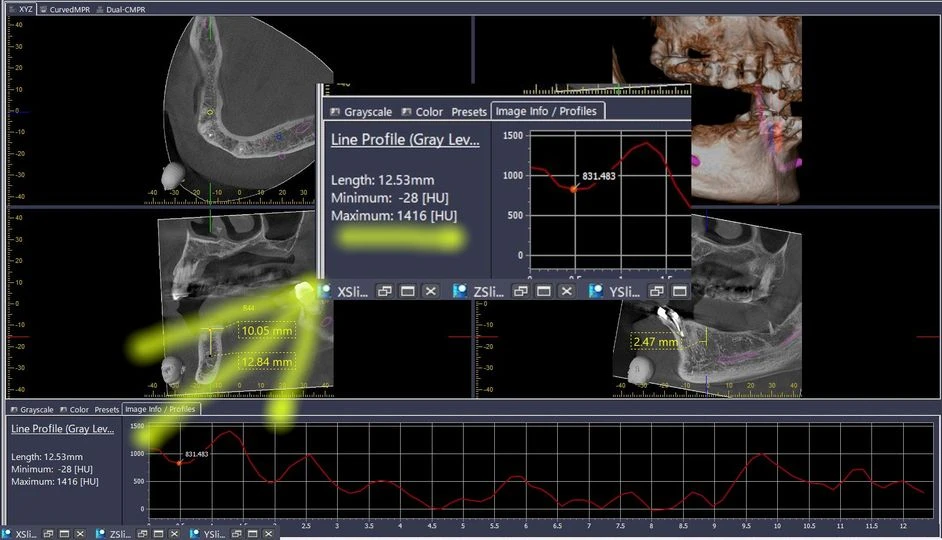

Điều đặc biệt của HU đối với thiết bị CBCT

Ứng dụng của HU trong CBCT rất quan trọng, chẳng hạn, khi khảo sát phim của một Implant mới cấy, đường đồ thị thể hiện chất lượng xương (HU) từ lớp xương vỏ, cắt ngang qua thân Implant có thể dễ dàng cho thấy sự tích hợp của xương quanh thân Implant đó như thế nào.

Tuy vậy, tất cả các CBCT hiện có trên thị trường khi hiển thị chất lượng xương đều không được phép hiển thị là đơn vị HU trừ CBCT của Morita. Các CBCT này chỉ hiển thị chỉ số dưới dạng “Profile”.

Bạn có thể tự mình kiểm chứng điều này khi sử dụng thang đo Profile trên các phần mềm CBCT (hay thang HU trên phần mềm i-Dixel Morita).

Các nha sĩ sẽ có được những con số chính xác và sát thực khi đo mật độ xương thông qua phần mềm i-Dixel. Từ đó, những trường hợp có HU nằm trong cấp độ D2, D3 sẽ thích hợp cho việc cắm Implant. Kết hợp khám lâm sàng và nhiều yếu tố khác, các nha sĩ hoàn thành ca cấy ghép một cách hoàn hảo và đảm bảo độ tích hợp xương sau điều trị.